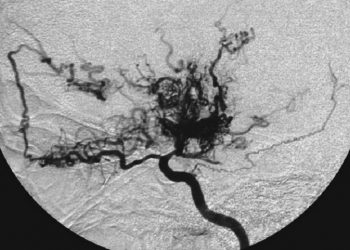

KENALI apa itu penyakit Moyamoya, beserta gejalanya. Penyakit Moyamoya adalah gangguan progresif yang menyebabkan penyempitan atau penyumbatan pada arteri karotis ...